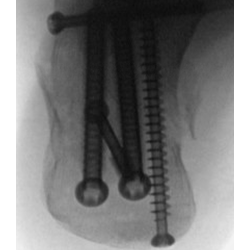

Your doctor will review your symptoms and medical history and conduct a thorough physical examination of your foot and ankle to check for range of motion, blood supply, and other signs of fracture. Your doctor may order a computer tomography (CT) scan in which images are taken from various planes to diagnose the degree of calcaneal injury. Foot X-rays may also be ordered which show the break in the heel bone or reduction in Bohler's angle (angles less than 20°, or more than 5° that is smaller than the uninjured side, indicate a fracture).

Surgery is recommended for intra-articular or displaced calcaneal fractures. The surgical procedure is called an open reduction and internal fixation (ORIF) and is performed under the effect of general anesthesia. Your surgeon will make an incision on the outside of the heel to expose the heel fracture. The fractured heel bones are placed together and fixed in place with a metal plate and multiple screws. This procedure minimizes the chance of developing arthritis and allows inward and outward movement of your foot. Your surgeon will plaster the foot to prevent movement of the ankle for a specified period of time to promote healing.